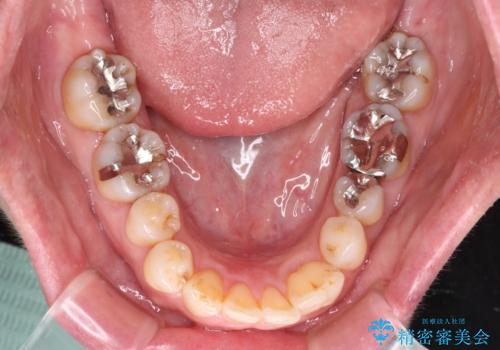

八重歯と形の悪い前歯 矯正治療とセラミック治療

また、当初は予定しておりませんでしたが、歯列が整ったことで前歯の歯の色や形が気になり、矯正治療後にオールセラミッククラウンにて補綴治療することとしました。

あっという間に気になっていた歯列が改善され、自然な口元になり、患者様には大変満足していただきました。